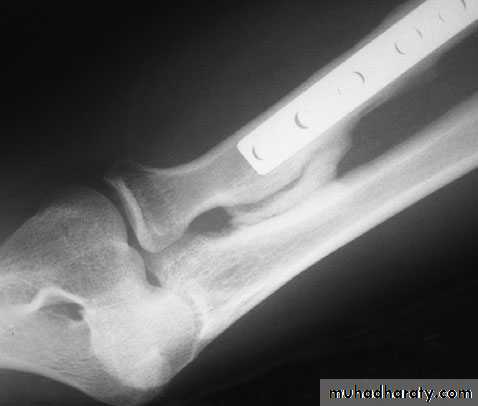

POST-TRAUMATIC STIFFNESS

OPERATIVE TREATMENT:

The indication is failure to regain a functional range of movement at 12 months

The objectives are determined by the type of pathology.

Heterotopic bone can be excised.

Capsular release or capsulectomy (open or arthroscopic),

fixing of ununited fractures or correction of malunited fractures.

Post-traumatic radio-ulnar synostos is treated by resection when the synostosis has matured (this takes about one year) followed by diligent physiotherapy